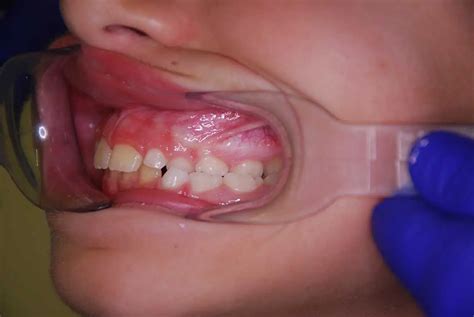

La mordida cruzada es una alteración que afecta al alineamiento de los dientes, ya que las piezas dentales superiores no encajan correctamente con las inferiores cuando la persona cierra la boca. En concreto, la mordida cruzada se produce cuando los dientes inferiores sobresalen respecto a los superiores y quedan por fuera.

En una oclusión correcta, los dientes de la arcada superior sobresalen por fuera de los inferiores. Sin embargo, en el caso de la mordida cruzada la mordida está invertida y los dientes de la arcada inferior están por fuera de los superiores.

- Mordida cruzada anterior: Afecta a los dientes anterosuperiores de canino a canino. Se puede observar en los dientes de leche, en los dientes permanentes, o en dentición mixta.

- Mordida cruzada posterior: Afecta a los dientes posteriores premolares y molares. Puede ser unilateral (de un único lado del arco dentario) o bilateral (en la que están afectados ambos lados del arco dentario).